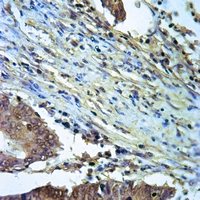

Immunohistochemical analysis of ALDH2 staining in human lymph node formalin fixed paraffin embedded tissue section. The section was pre-treated using heat mediated antigen retrieval with sodium citrate buffer (pH 6.0). The section was then incubated with the antibody at room temperature and detected using an HRP conjugated compact polymer system. DAB was used as the chromogen. The section was then counterstained with haematoxylin and mounted with DPX. -